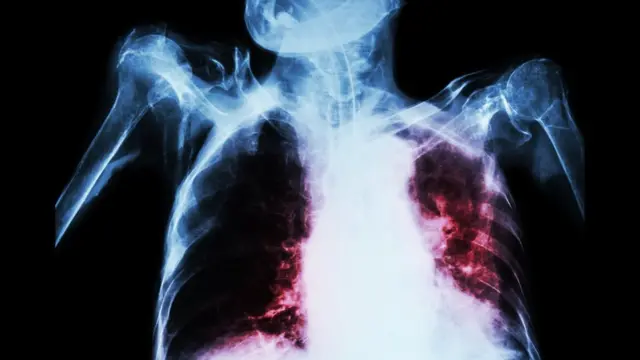

शोधकर्ताओं ने ट्यूबरकुलोसिस (टीबी) की ऐसी वैक्सीन खोजी है जो इसके इलाज में क्रांति ला सकती है.

बेहद संक्रामक यह रोग बैक्टीरिया की वजह से होता है और इसके इलाज के लिए दुनिया भर में दिया जाने वाला बीसीजी का टीका उतना कारगर नहीं है.

- मुख्य रूप से यह फेफड़ों को प्रभावित करता है लेकिन इसके साथ ही यह शरीर के किसी भी हिस्से को प्रभावित कर सकता है, जैसे कि पेट की ग्रंथियां, हड्डी या तंत्रिका तंत्र (नर्वस सिस्टम).